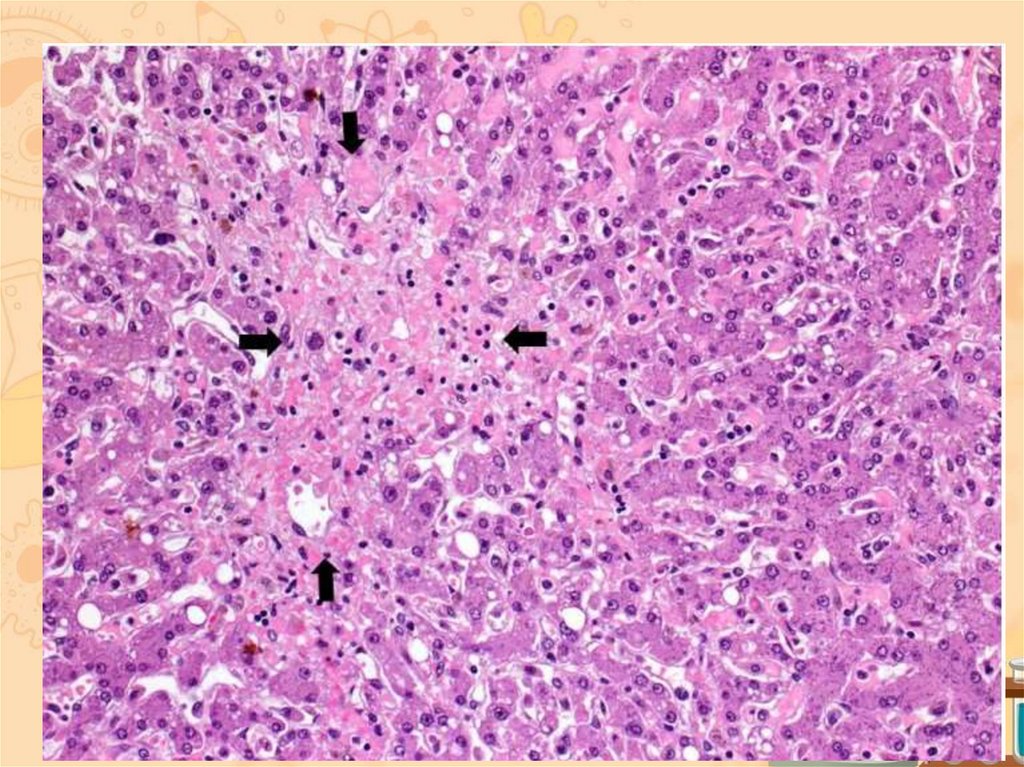

17. ПЕЧЕНЬ

18.